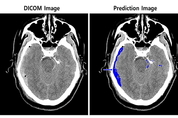

[엔트로피타임즈 민경종 기자] SK㈜ C&C의 ‘뇌출혈 영상 판독 AI 모델’이 최근 GMP 인증을 획득해 촌각을 다투는 뇌출혈 환자의 골든타임 사수에 도움을 줄 날이 머지않은 것으로 보인다. 지난 18일 SK㈜ C&C(대표 박성하)가 자사 ‘뇌출혈 영상 판독 AI 모델’이 의료 기기 제조 및 품질 관리 기준(GMP) 적합 인증을 획득했다고 밝힌 것인데, GMP(Good Manufacturing Practice)는 의료기기 제조업자가 생산하는 의료기기의 안전성 및 유효성을 확인, 의도된 용도에 적합한 품질로 일관성 있게 생산할 수 있는지를 보증하기 위한 품질 보증체계다. 의료기기 제조를 위한 원료 구입부터 제조, 출하 등에 이르는 전 과정에 걸쳐 필요한 관리 기준을 규정하고 있으며, 식품의약품안전처에서 관리하고 있다. SK㈜ C&C는 이번 GMP 인증 획득 후 임상시험 계획(IND)을 식품의약품안전처에 제출해 심사를 받고 있으며, 올해 안에 다수의 기관에서 임상시험을 실시할 예정이다. 그동안 SK㈜ C&C는 1차 아주대학교의료원에 이어 2차로 서울대학교병원의 CT 영상을 활용해 ‘뇌출혈 영상 판독 AI모델’을 개발했다. 이 모델